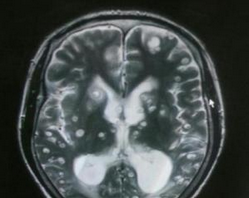

摘要:脑囊虫病是由寄生虫(猪绦虫为主)所传染的一种顽固性颅脑内疾病。该病约占囊虫病的80%以上。尽管使用新型MRI扫描序列,有些脑囊虫病囊肿依然被隐藏。本研究评估钆双胺(GDD)-MRI脑室造影在鉴定脑囊虫病病例中的诊断价值。结果表明,钆双胺-MRI脑室造影有助于蛛网膜下和脑室内脑囊虫病的诊断,同时能提高诊断准确性。 关键词:脑囊虫病,诊断价值,钆双胺-MRI脑室造影,准确性

脑囊虫病是由寄生虫(猪绦虫为主)所传染的一种顽固性颅脑内疾病。该病约占囊虫病的80%以上。尽管使用新型MRI扫描序列,有些脑囊虫病囊肿依然被隐藏。本研究评估钆双胺(GDD)-MRI脑室造影在鉴定脑囊虫病病例中的诊断价值。结果表明,钆双胺-MRI脑室造影有助于蛛网膜下和脑室内脑囊虫病的诊断,同时能提高诊断准确性。相关报告2015年发表在《Trop Med Int Health》。 在该项研究中,研究人员纳入年龄18-65岁的疑似蛛网膜下囊虫病患者,这些患者在先前的神经影像学检查中不能证明囊肿的存在。鞘内注射1mL GDD作为MRI检查的对比剂。 研究共纳入14名患者。在9名患者中达到最佳的对比剂扩散,4名患者对比剂部分扩散。10名患者被鉴定为颅内囊泡,总共发现超过60个轻度蛛网膜下囊泡,4名患者的5个囊肿在第四脑室,1名患者的1个流动囊肿在侧脑室。在1例病例中,鞘内GDD证实脊髓囊虫病。鞘内给药GDD后无不良事件报告。 结果表明,鞘内注射GDD有助于蛛网膜下和脑室内脑囊虫病的诊断,同时能提高诊断准确性。 (环球医学资讯供稿 责任编辑 :Ada) 参考资料:http://www.ncbi.nlm.nih.gov/pubmed/25726723